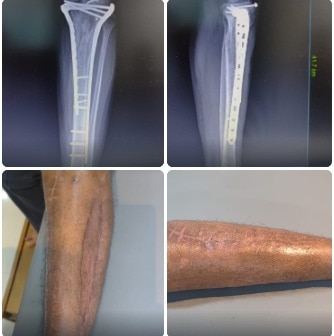

Sunshine Ortho Pain Superspeciality Hospital is the Best Multispeciality Hospital, Orthopedic Hospital in Wakad, Hnjewadi, PCMC and Pune. We are specialized in Orthopedic Surgeries, Robotic Joint Replacement Surgery, Hip and Knee Replacement Surgery, Complex Trauma And Pelvi Acetabular Surgery, Spine Surgery, Sports Medicine And Arthroscopy, Regenerative Therapy/Prolotherapy, Shoulder Surgery, Knee Surgeries, Foot And Ankle Treatment in Wakad, Hinjewadi, PCMC and Pune.